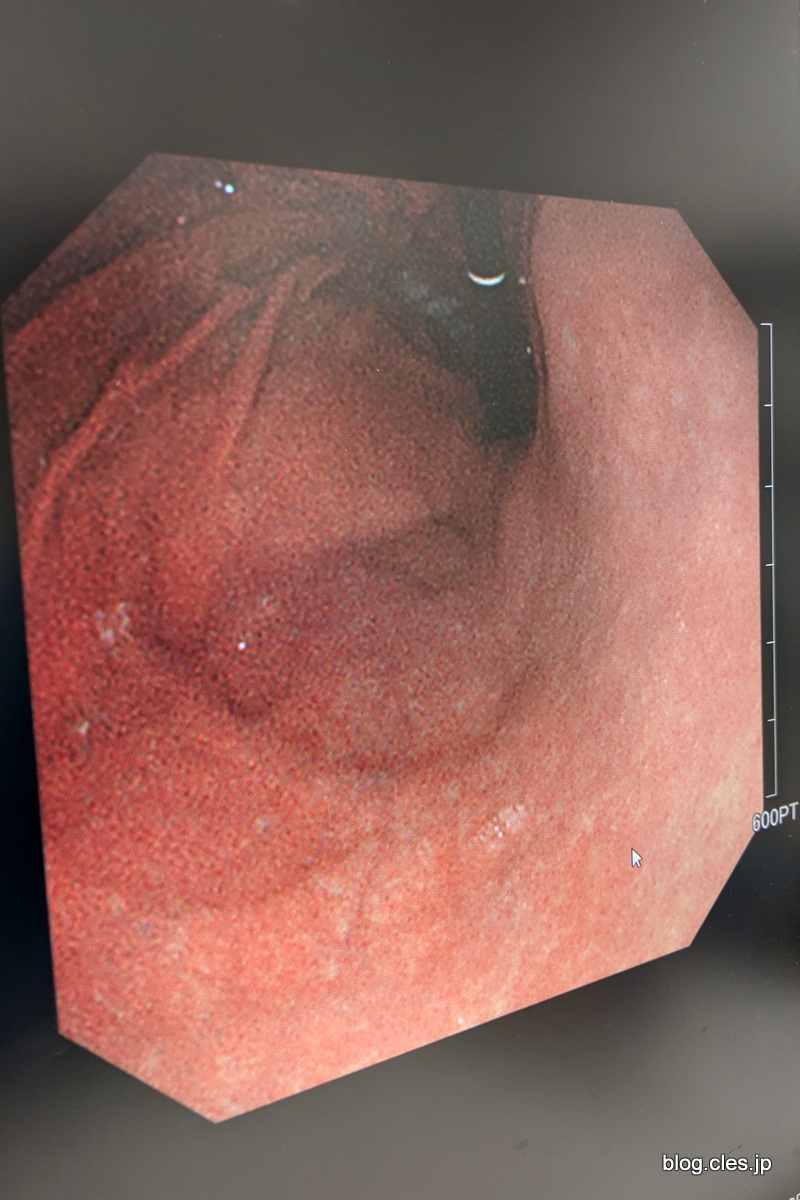

胃カメラの画像+-+今日からピロリ菌の除菌を開始